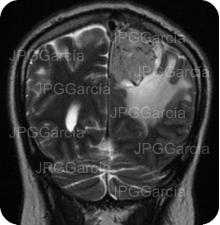

Estudio de IRM de cráneo mostrando una lesión tumoral hacia el tercio posterior de la hoz cerebral relacionado a un meningioma